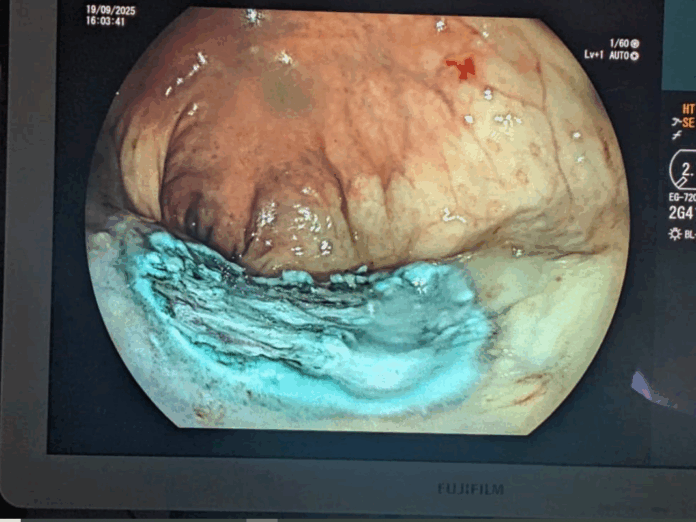

Uburyo ESD ikorwamo ni ugufata ‘tube’ iriho camera n’utundi dukoresho bijyana bakayinjiza mu mubiri bayinjujije ahaca imyanda yo mu musarane noneho bakayigeza aho babonye ya kanseri.

Iyo ‘tube’ iba ihuje na mudasobwa zabugenewe kandi irimo n’inzira inyuramo amashusho y’ako kanya ya camera iri gufata ku buryo abaganga babona neza aho kanseri iri kandi bakabasha kuyikuramo badakomerekeje ibindi bice.

Iyo agace gafite kanseri bamaze kugakuramo bagasohora hanze bakajya kugapima muri laboratwari ngo bamenye neza niba ishizemo.